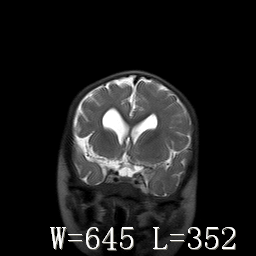

标题: PED3252:脑室增大。

女,3岁,3岁不会说话,阵发性抽搐、自伤。

考虑为梗阻性脑积水(中脑导水管狭窄)。

脑积水?脑发育不良?

侧脑室不规则,前后角尖角样,脑白质较少:考虑灰质发育不良可能

考虑,脑发育不良,胼胝体发育不全?(图片不全,矢状位?)